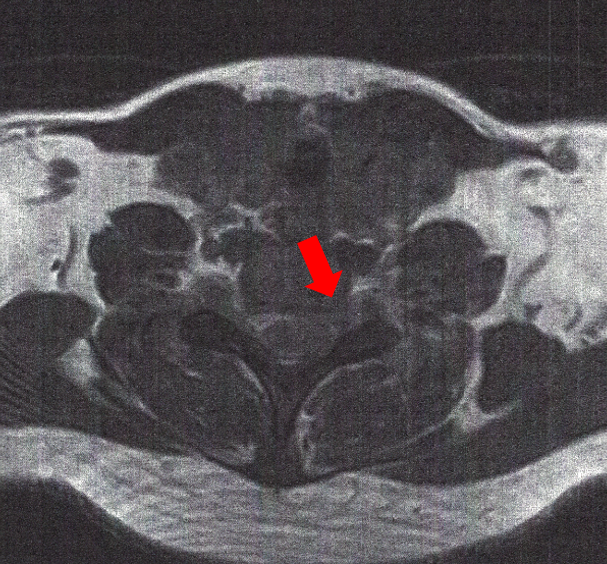

risonanzafreccia

Cefalea catameniale in cervicobrachialgia sx.